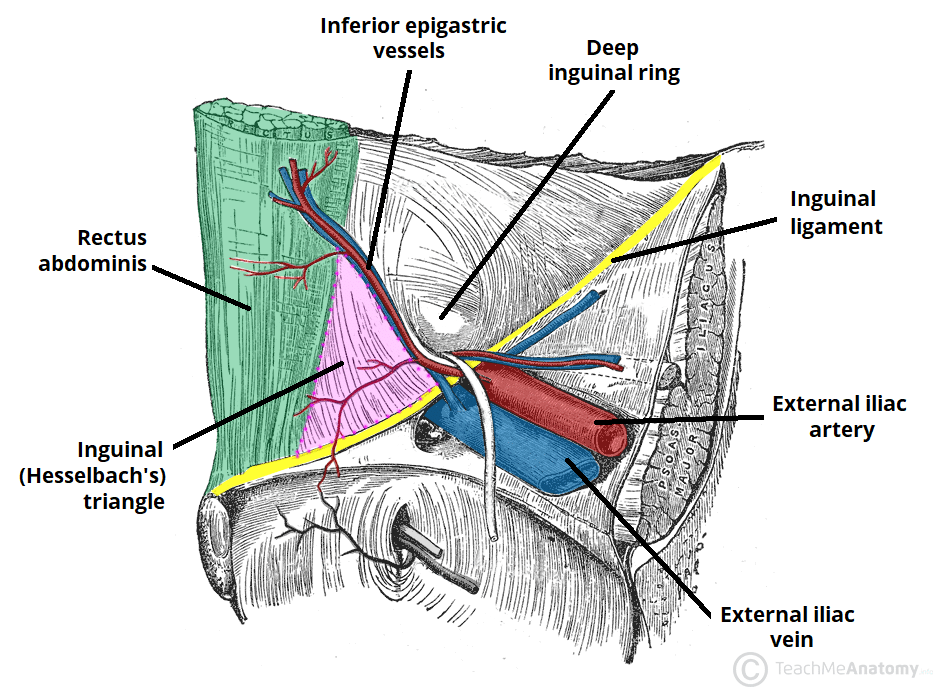

Inguinal triangle (Hesselbach)

Vessels and nerves at risk for injury in anterior abdominal wall